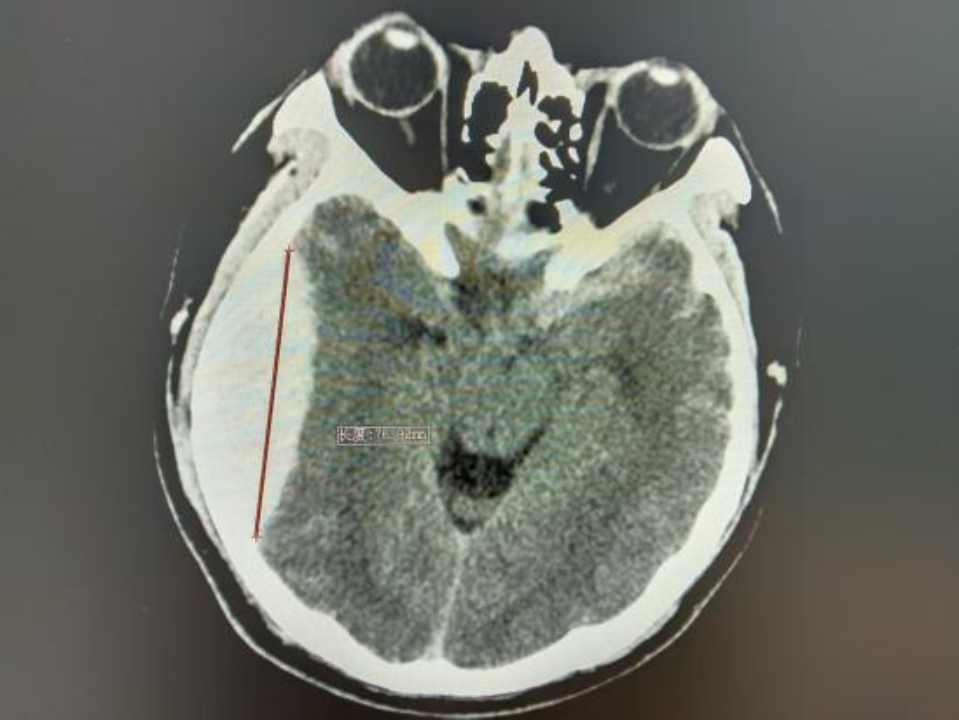

△术后颅脑CT

近期,北大人民青岛医院神经外科团队在北京大学人民医院神经外科专家刘波带领下,常态化开展神经内镜下硬脑膜外血肿清除术。其中一位19岁的年轻小伙,驾驶摩托车不慎摔伤,伤后头痛、头晕、恶心,头痛呈进行性加重,逐渐开始出现意识障碍,到青岛医院急诊行颅脑CT检查后证实为创伤性硬脑膜外血肿,神经外科团队予以急症状态下神经内镜下硬脑膜外血肿清除术手术治疗,目前患者已经康复出院。

传统的手术方法是“问号形”或“马蹄形”切口切开头皮,根据血肿范围切除相当的骨瓣清除血肿,创伤大,切口一般在20cm左右,出血多,恢复慢。北京大学人民医院青岛医院采取神经内镜下清除硬脑外血肿,小切口,小骨窗,术中出血少,病人恢复快。